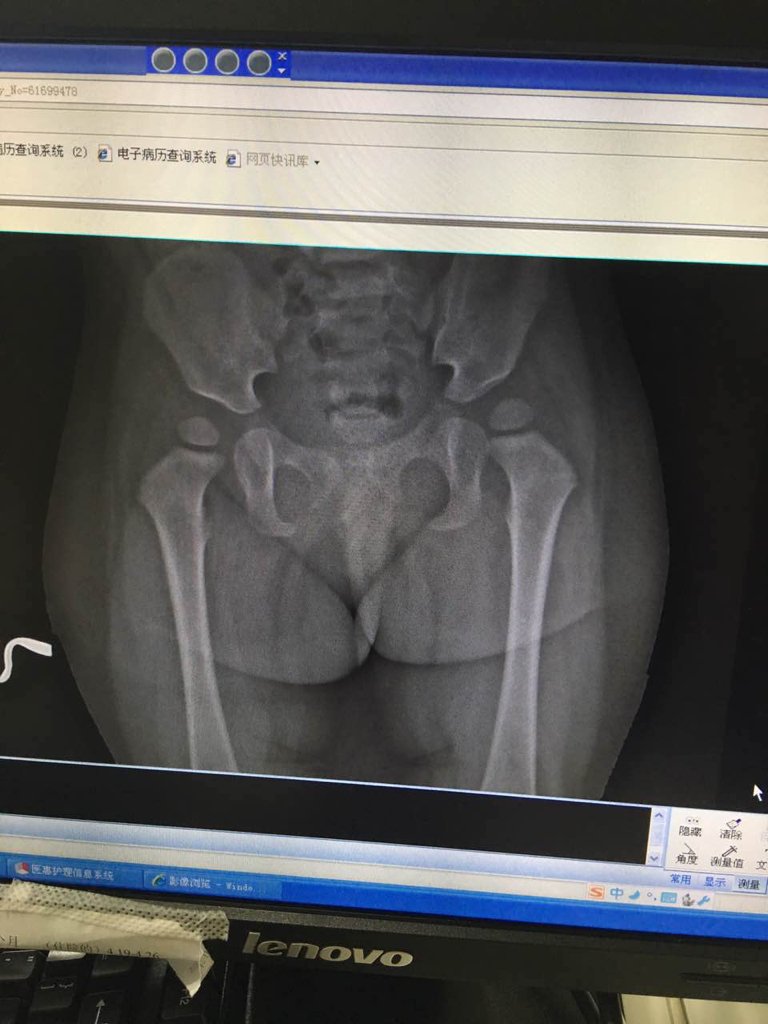

婴儿盆骨上骨骼发育不良 乡下医生说那个要买那个两千块的矫正器 真的需要吗 点击展开 137*****890_KzYn 2016-06-20 23:09 满意回答 你好医顿,根辨清据照片提示,这应该是髋臼发育不良,是需要蒸顿之买个矫正器的。 cn#BkLVkQfkku 2016-06-20 23:10 宝宝知道提示您:回答为网友贡献,仅供参考。 相关问题 骨骼发育不良是不是脑瘫?怎么矫正? 宝宝23天B超髋关节发育不良带蛙式矫正器能够更好更快的矫正吗 我朋友最近一直出现软骨发育不良与骨骼畸形智力发育迟…